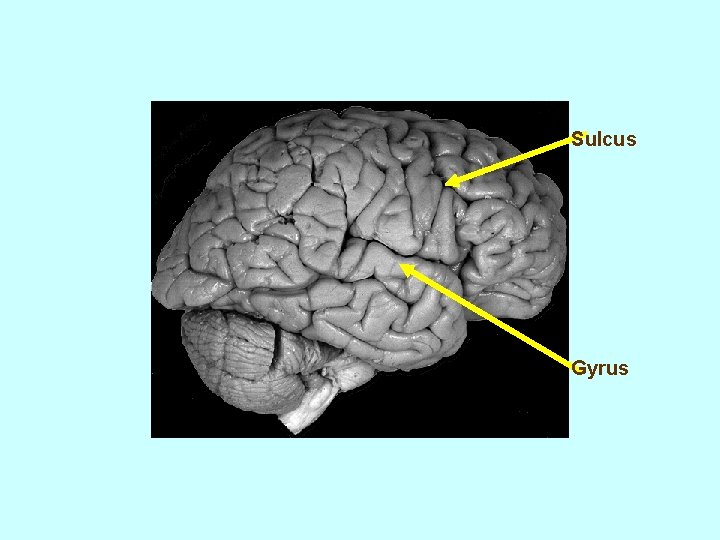

Sulcus Gyrus